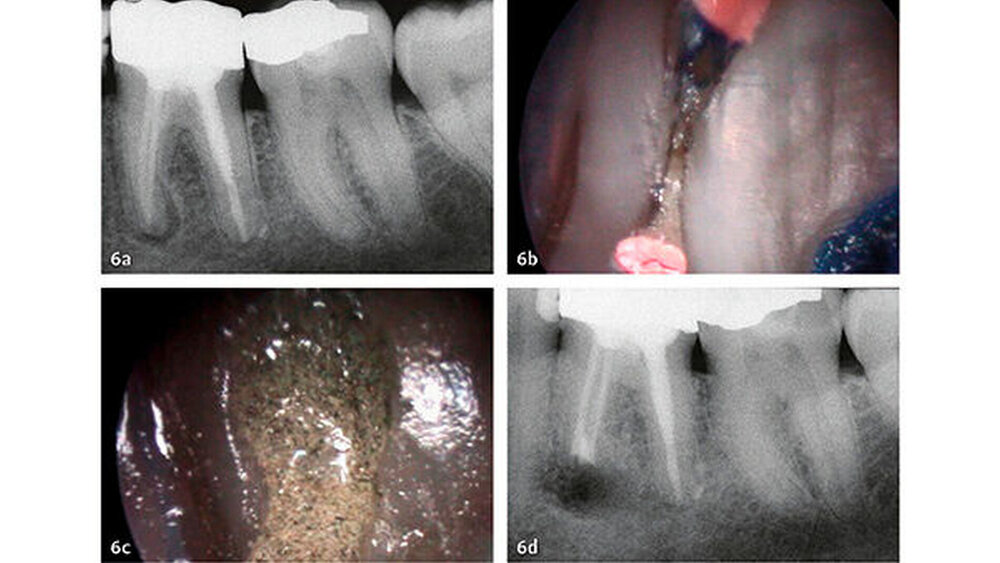

Klinische Studien

Die wesentlichen Daten von klinischen Studien über die Anwendung von MTA als retrogradem Füllmaterial sind in Tabelle III zusammengefasst. Die erste klinische Studie mit Auswertung der Erfolgsrate nach MTA-Anwendung in der apikalen Chirurgie wurde von Chong et al. (2003) publiziert - es war auch gleich die erste randomisierte Studie, welche MTA mit einem anderen retrograden Verschlusszement untersucht hat. Generell zeigen alle klinischen Studien sehr hohe Erfolgsraten für MTA in der apikalen Chirurgie (83,7% bis 96%). Die von uns 2014 publizierten Langzeitdaten (5 Jahre Beobachtungsdauer für alle behandelten Zähne) mit einer Erfolgsrate von 92,5% deuten auf eine sehr gute Stabilität und auf ein hohes Abdichtungsvermögen von MTA (von Arx et al. 2014) (Abb. 4 und 5).

Die Dokumentation der 10-Jahresdaten ist im Gange, und die bisherige Analyse deutet auf eine konstant hohe Erfolgsrate auch nach zehn Jahren (Abb. 6). Eine systematische Auswertung mit Meta-Analyse aller bis 2007 publizierten retrograden Füllmaterialien in Vergleichsstudien mit mindestens zwei getesteten Verschlussmaterialien ergab für MTA die höchste Wahrscheinlichkeit einer periapikalen Ausheilung (91,4%) (von Arx et al. 2010a).